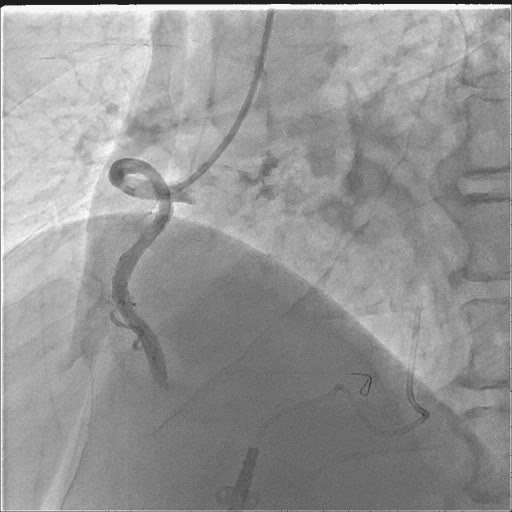

暂时缓解了心脏压塞,但迂曲的血管,是下一个难关!导丝、球囊根本不能到位,在延伸导管的帮助下完成球囊扩张及支架植入。

支架植入也是非常困难,最后经过深插GC,延伸导管尽量靠前支撑下,完成了支架植入。开通后可以发现RCA非常大,范围很广。